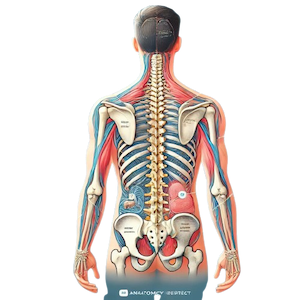

Our Spine Injury Attorneys Are Ready to Help

Spine injuries are some of the most devastating injuries a person can suffer. They can lead to lifelong disabilities, ongoing medical care, and a significant impact on your quality of life.

We Know Spine Injuries

Types of Spine Injuries

The spine is a delicate and complex part of the body. Damage to any part of the spine cord can result in serious and lasting injuries. Common types of spine injuries include:

- Paraplegia: Partial paralysis, typically affecting the legs, occurs when the lower part of the spine cord is damaged.

- Quadriplegia: Full paralysis affecting all four limbs and the torso, which results from damage to the upper portion of the spine.

- Herniated discs: When the discs between the vertebrae become damaged or displaced, it can cause intense pain, numbness, and mobility issues.

- Fractured vertebrae: Broken vertebrae can pinch or sever the spine cord, leading to paralysis or significant nerve damage.

- Whiplash: Common in car accidents, whiplash can strain or tear the ligaments and muscles in the neck and upper back, often leading to long-term pain.

Why Spine Injuries Require Long-Term Care

Unlike some injuries, spine cord damage often requires lifelong treatment and rehabilitation. A spine injury can lead to partial or full paralysis, affecting your ability to perform daily activities or work. Many spine injury victims need specialized medical care for years, if not for the rest of their lives. Treatments may include: